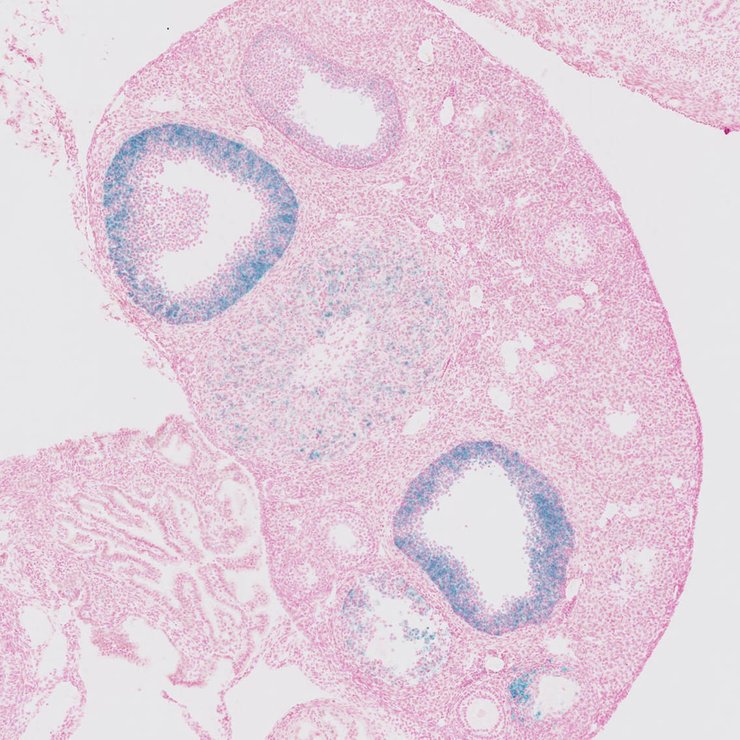

TS28: ovary Present JAX_1124137